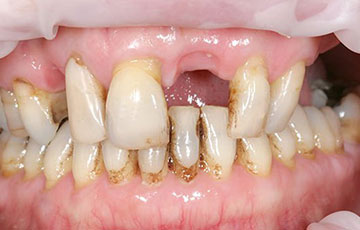

このような症状でお悩みの方は、

一度当院へご相談ください!

重度の虫歯や歯周病で歯が強く揺れている場合、無理に残しても十分に噛めないことがあります。そのようなケースでは、オールオン4が検討されます。安定した噛み心地と自然な見た目を両立でき、口腔内環境の改善につながります。

- 原則として残存歯を抜歯する

- オールオン4では、基本的に残っている歯を抜歯し、インプラントで全体を支える設計となります。ただし、残存歯の状態が不良で十分に機能していない場合は、無理に保存するよりも固定式の人工歯へ移行した方が、結果的に安定した咀嚼機能を得られることが多くあります。